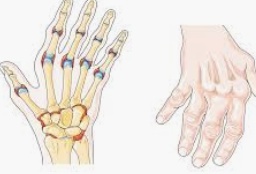

개인마다 차이는 있지만 대부분 아픈 통증이 발생하는 상황도

다양한 편인데 자고 일어나면 관절이나 근육이 많이 굳어있고

특히 목이나 어깨 무릎 같은 부위에 통증이 심한 경우가 많습니다.